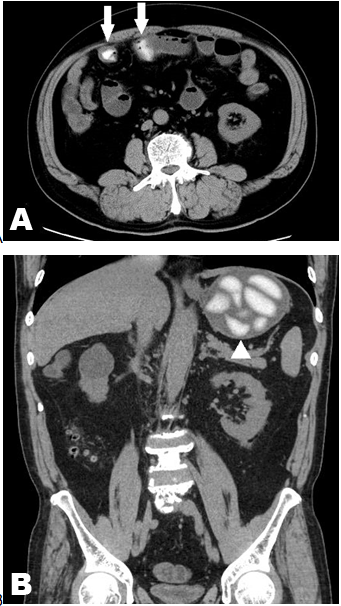

A 67-year-old male with no significant past medical history was referred to the hospital complaining of abdominal pain. Eighteen hours prior to admission, he ate four pieces of rice cake (mochi in Japanese) and after six hours, he ate four pieces of rice cake again. Nine hours prior to admission, he noted intermittent abdominal pain with one vomitus. He visited his general practitioner. Physical examination at the general practitioner suggested small bowel obstruction. He was referred to the hospital for further investigation. On physical examination, he had mild tenderness in upper abdomen without peritoneal signs. A small bowel obstruction due to rice cake was suspected. The abdominal computed tomography (CT) scan, revealed high density materials in the stomach and the small intestine with proximal intestinal dilation (Figure 1A-B). This typical appearance made the final diagnosis of small bowel obstruction due to rice cake and he admitted to the hospital for observation. His symptoms disappeared without specific treatment and he discharged from hospital on the third day from admission. |

Small bowel obstruction (SBO) is a common disease encountered in daily practice. The causes of SBO can vary. In the review of unusual causes of SBOs, 60% of them are caused by adhesions, followed by hernias 15%, neoplasms 6%, inflammatory causes 5%, mesenteric vascular occlusion 5%, intussusception 3%, and unusual etiology 6%. [1]. Matsuzaki et.al. reviewed 193 patients of SBOs induced by food in Japan [2]. The most frequent causative food is seeds or stones fruit, followed by rice cakes, seaweed, agar or gelatin food made from devil's tongue starch. The patients are often associated with previous abdominal surgery, especially gastrectomy. Dental disorders such as problems with chewing or artificial teeth, unusual eating habits like swallowing without chewing, and irradiation to abdominal cavity can also be contributing factors. Rice cakes are often eaten in Japan. Especially in the New Year's Holidays, because Japanese people have a tradition to eat rice cakes in those holidays. Miura et al. reviewed 14 patients of SBO caused by rice cake [3]. Ten out of fourteen patients have a history of previous abdominal surgery and all patients had ingested rice cake by swallowing without chewing. In this patient, interestingly, he had no contributing factors like previous abdominal surgery or unusual eating habits. The diagnosis of SBO induced by food is generally difficult. However, the diagnosis of SBO due to rice cake can easily be obtained by CT scan. The rice cakes are typically visualized as high density materials in the alimentary tract [3]. Treatment of rice cake induced SBO should be non-operative management, with occasional decompression by a nasogastric tube and fluid supply. All patients can be successfully treated by non-operative management in the recent review, as in the present patient [3]. However, chronic symptom could possibly cause ulcer or intestinal perforation so careful following-up should be considered. |

Small bowel obstruction due to rice cake is a relatively rare disease. Careful history taking is essential and computed tomography scan demonstrates typical appearance of high density materials. |